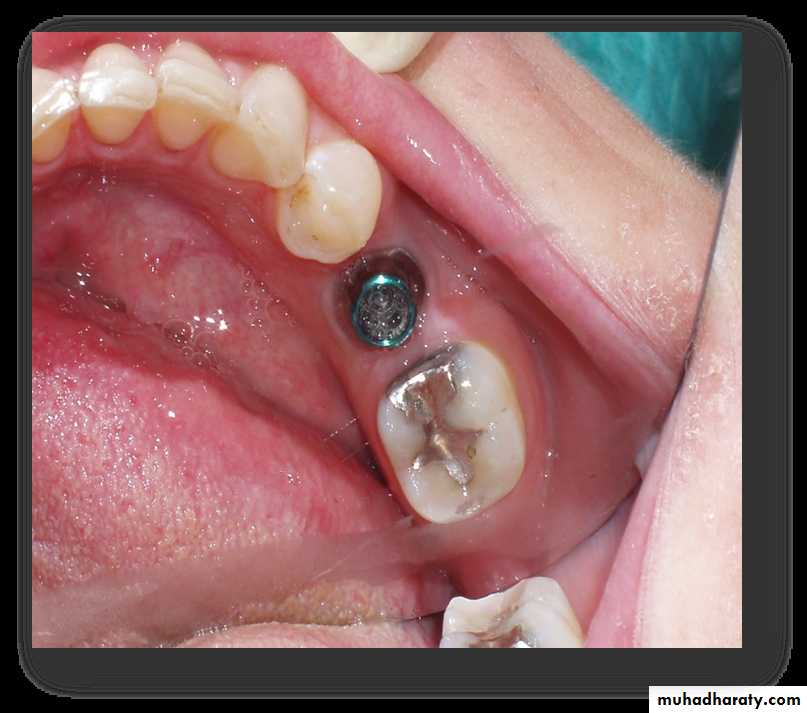

Endosteal / Endosseous Implants

• Extends into basal bone for support• It transects into 1 cortical plate

C. Root form implantThe most popular implants in the world today.

come in a variety of shapes, sizes, and materials

can be placed wherever a tooth or several teeth are missing when enough bone is available to accommodate them.